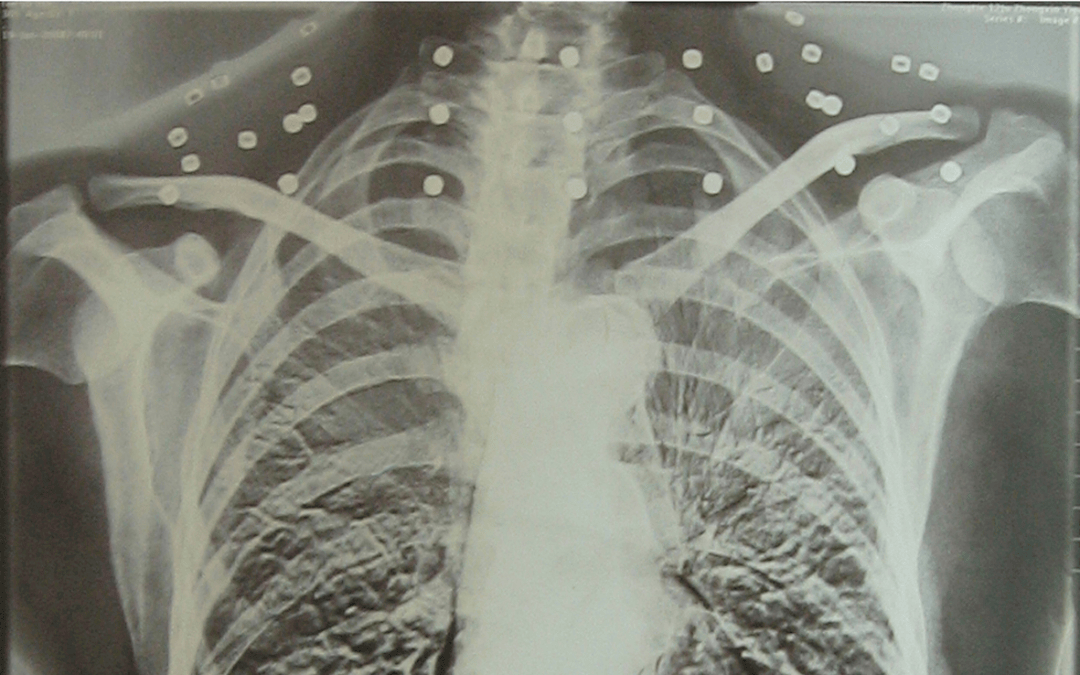

这张照片

是今年82岁的吴以先老人

拍摄的一张CT照

20年前

吴以先在一次做CT检查时

医生误以为皇冠信用怎么弄 他戴了项链

于是提醒要取下来再做检查

但实际上是

吴以先的颈部和腹部

共分布着33枚弹片